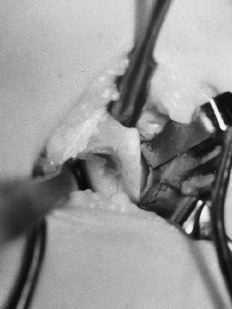

En el estudio radiológico se apreció una prominencia ósea situada en la cara anteromedial del húmero, a unos 5 cm por encima de la epitróclea, cuyo tamaño era de unos 2 cm de largo, de base ancha y forma alargada dirigida en dirección inferior y anterior (Fig. 1). Ante el diagnóstico de apófisis supraepitroclear, y debido a la clínica neurovascular que presentaba la paciente, se optó por el tratamiento quirúrgico.

ABFigura 1. A: Rx AP. Se aprecia la apófisis supraepitroclear en dirección craneocaudal y hacia medial. B: Rx lateral.